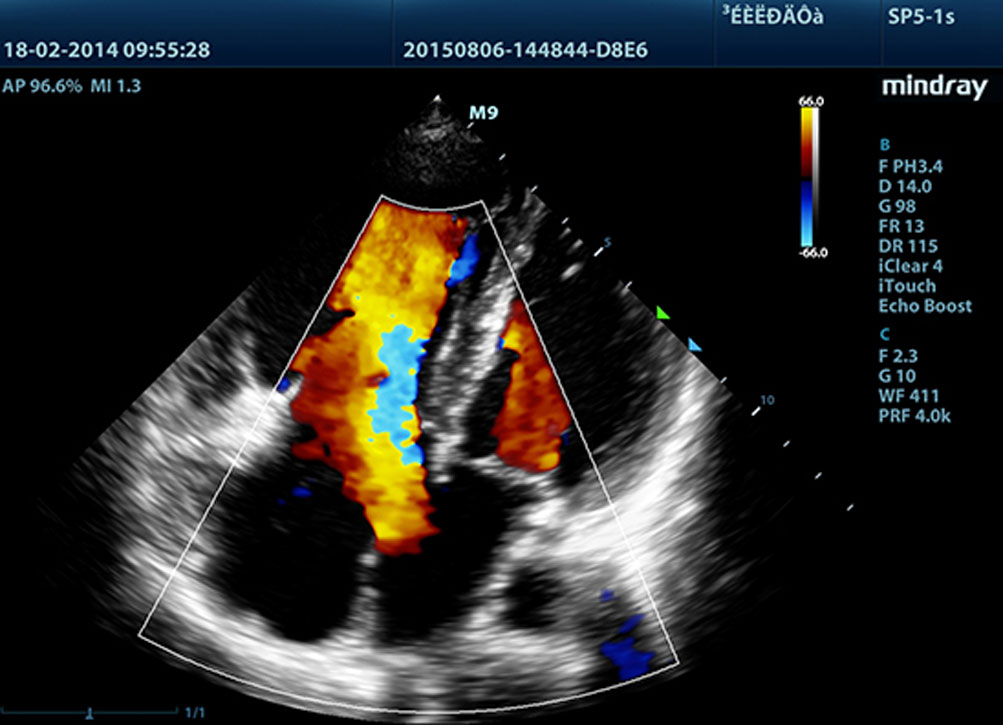

Proporcionando imĂĄgenes mĂĄs nĂtidas, todas las sondas compatibles con el M9 vienen equipadas con la tecnologĂa de transductor 3T Ășnica de Mindray. Mejorado con el a?adido de la tecnologĂa de cristal Ășnico, el M9 ofrece una mejor penetraciĂłn y flujo dinĂĄmico de color, especialmente durante escaneado de pacientes difĂciles.

LVO con ecocardiografĂa de estrĂ©s

Las capacidades superiores del M9 permiten la opacificaciĂłn LV durante el estrĂ©s, lo que mejora la discriminaciĂłn entre tejidos miocardiacos y coĂĄgulos de sangre y proporciona una mejor visualizaciĂłn de la superficie endocardiaca. La funciĂłn de ecocardiografĂa de estrĂ©s del M9 incluye un paquete completo para ecocardiograma de estrĂ©s farmacolĂłgico y de ejercicio. El paquete estĂĄ soportado por un sistema de informe flexible que puede ser optimizado para sus necesidades individuales.